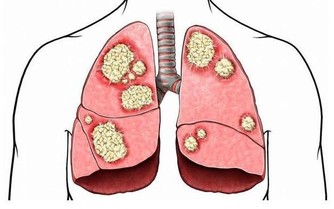

是由於變老的生理變化和病理變化,使患病的機率升高,衰老本身就是許多疾病的風險因素。

所以,變老不僅包括機體生理上的衰退,也包括在這個過程中發生的病理變化。

但是機體的這些病理變化,在沒有達到一定量的時候可以不發病;

只有病理變化累積達到一定程度,機體自身無法修復或及時修復的時候,才會出現生病的症狀。